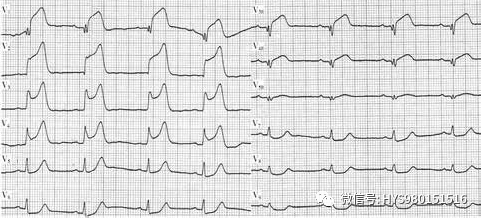

一次心动周期就会在新电图上记录出一系列地高低宽窄不同的波形。

包括P波、QRS波群、T波和(无)u波。了解这些波形及其所代表的意义,是教你怎么看心电图的第二步。

P波,最先出现的一个振幅不高的圆钝波形,它记录的是窦房结激动的右、左心房的激动。因为窦房结位于右心房,心房的激动先由它开始,所以P波的前半部分记录的是右心房的激动,

中间部分记录的是左、右心房的共同激动而后部则代表左心房的激动。除了aVR导联外,P波基本都是直立的,肢体导联中P波的高度多不超过0.25mV,胸前导联中直立的P波高度不应超过0.15mV。正常的P波的宽度也不应超过0.11s。

QRS波群,继P波之后出现的一个狭窄但振幅高的波群。由q波(有或无)、R波和S波组成。它代表着兴奋从房室结发出先后通过房室束、左右束支和纤细的浦肯野纤维进入心肌细胞,刺激心室的收缩,因此可以将其看作是心室收缩的开始的心电图表现。

Q波,是在出现向上的波之前出现的明确的向下的波形。如果它很小,宽度不到0.04s,深度不足0.15mV,我们将它记做q波;若它高且宽,才被称作Q波;当然有时它是缺无的。

无论有无Q波,第一个出现的向上的高尖的波就是R波;紧随其后的向下的波就是S波,它也可以根据深度分别命名为S波和s波。

之后出现的向上的波被称作R’(r’)波,向下的波则称作S’(s’)波。因为波的高低不同,所以可以组合成很多形态,但它也是有限制的,最主要的就是时间限制,通常情况下,正常人的QRS波群的时间0.08s,可以在0.06~0.10s范围内波动。只要超过这个时限,就应引起注意,特别是超过0.12s便有病理意义了。

T波,上个波群暂停之后出现的波,代表着心室的复极(心室的舒张),以备下一次心室的除极。观测T波我们要注意它的方向、形态和(高度)深度。

(1)方向,正常情况下,在Ⅰ、Ⅱ导联中T波是直立的;Ⅲ导联中则可以出现直立、平坦、双向甚至是倒置的T波;T波在aVR导联中是肯定倒置的,而在aVL和aVF导联中则是和QRS波群的主方向一致的。胸前导联的T波通常是直立的,当然,V1和V3有时也会出现T波倒置的情况,但它们的深度通常都不会超过0.25mV,当V3导联中出现倒置的T波时,前面两个导连的T波也应该是倒置的,否则就是不正常的表现。

(2)形态,通常T波的波形是圆滑而有个很自然的顶端。T波一般是不对称的,缓和的上升而略显陡峭地下降至等位线。

(3)高度(深度),各个导联并不完全相同,不过综合看来,在肢体导联中很少超过0.5mV,而在胸前导联中也很少会超过1.0mV。异常高尖的T波往往出现在心肌梗死的早期或高钾血症。

U波,T波后的一个很微小的波,正常的u波并不是在每一个导联中都显而易见,它究竟代表什么尚无定论。

每个波形之间都有一定时间的记录是在等电位线上的,分别被称作P-R间期、S-T段和Q-T间期,它们也都有着各自存在的意义。熟悉了解这些间期代表的意义是知道怎么看心电图的第三步。